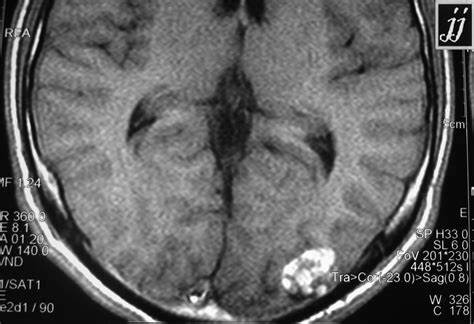

腦海綿狀血管瘤(CMs)是一種血管畸形,由薄的透明血管通道組成,沒有腦實(shí)質(zhì)的介入。這些病變周圍有含鐵血黃素沉積和膠質(zhì)細(xì)胞邊緣,可能是血栓形成了其位置是可變的,70%-80%的顱...

腦海綿狀血管瘤(CMs)是一種血管畸形,由薄的透明血管通道組成,沒有腦實(shí)質(zhì)的介入。這些病變周圍有含鐵血黃素沉積和膠質(zhì)細(xì)胞邊緣,可能是血栓形成了其位置是可變的,70%-80%的顱內(nèi)CMs起源于幕上。

隨著磁共振成像技術(shù)的日益普及,CM的診斷率也有了很大的提高。事實(shí)上,在磁共振成像之前,CMs并不常見,其評(píng)估和處理僅在病例報(bào)告和小型臨床系列中描述。這些血管病變?cè)谠\斷性血管造影中并不明顯,因?yàn)樗鼈兊男再|(zhì)是低壓系統(tǒng),因此被稱為血管造影隱匿性血管畸形。然而,影像學(xué)的好轉(zhuǎn)不僅增加了對(duì)癥狀性病變的診斷,而且偶然發(fā)現(xiàn)了CMs,其中40%是偶然發(fā)現(xiàn)的。與CMs相關(guān)的不同風(fēng)險(xiǎn)是出血或微出血的發(fā)生,這些出血或微出血可導(dǎo)致死亡、神經(jīng)功能缺損、癲癇,或者可能根本沒有臨床缺陷。